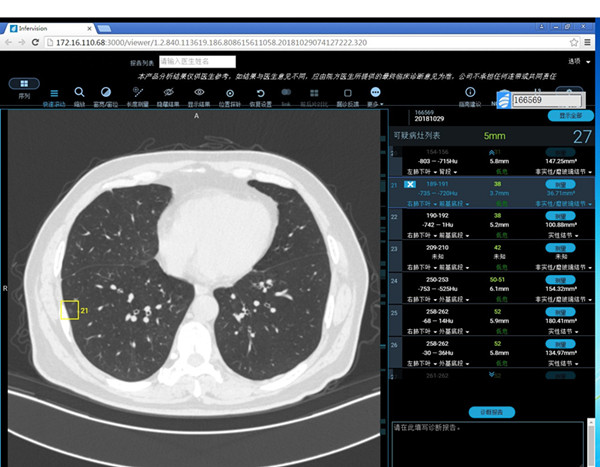

近日,我院在肺结节CT筛查时,正式启用人工智能AI技术!

AI技术全称Artificial Intelligence技术,是CT界的“阿尔法狗”,被誉为医生的第二双眼睛。它是智能的“肺结节医生”,主要是基于CT肺部扫描后增加对肺内结节性病灶的检出及良恶性做出初步判断,再由影像科高年资医生对其结果进行审核,去除其部分假阳性或假阴性结果,从而得到一份较为准确的报告。

该系统的应用将提高肺小结节的检出率,避免人眼不易识别结节的漏诊,提高诊断的准确性、减少漏诊率。

据统计,人工智能肺结节筛查系统可达到主治医师的水准,能辅助影像科医生快速做出诊断,提高工作效率和减少漏诊率。